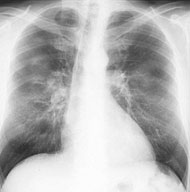

Ein 58-jähriger, sportlich aktiver Mann sucht Sie in der Sprechstunde auf. Er klagt über eine Leistungsminderung und Husten mit etwas weisslichem Auswurf seit ca. 2-3 Wochen. Dazu subfebrile Temperaturerhöhung.

In der Anamnese erfahren Sie, dass der Patient früher geraucht hat (30 packyears), seit 10 Jahren allerdings nicht mehr. Kardiopulmonale Vorerkrankungen werden verneint. Die Lungenauskultation zeigt keine pathologischen Befunde.

Sie beschliessen, ein Thorax-Röntgenbild durchzuführen:

Wie beurteilen Sie das Röntgenbild in Kombination mit der Klinik?